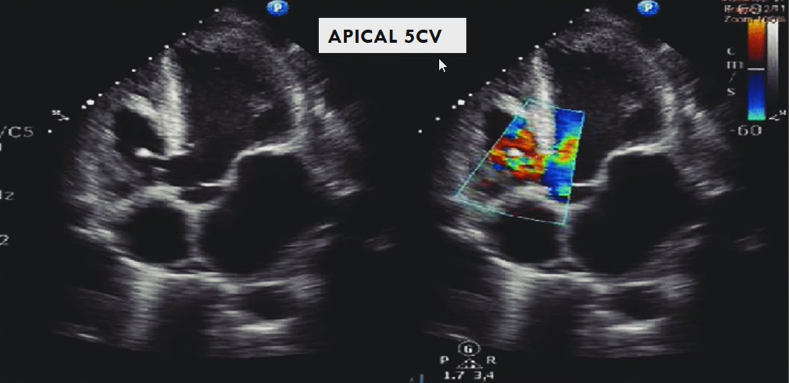

DX

A

Perimembranosus septsal deffect

5C, basal is perimembranosus and mind an apical is trabecular